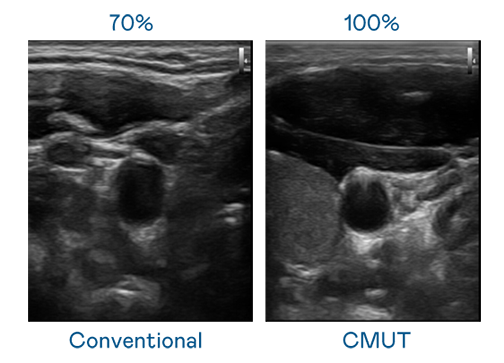

CMUT 技术是一种用电容式微机电元件来产生超音波讯号的技术。与传统 PZT 压电式技术相比,CMUT 频宽增加 30%,更宽频的超音波讯号让影像解析度大幅提升,是实现高影像品质医疗超音波扫描、促进精准医疗发展的关键技术。

大频宽带来超清晰影像

超音波影像的解析度高低,首先取决于探头能发出的讯号频宽。星空电子 CMUT 可提供高清晰的超音波讯号,提供高频宽、高灵敏度、影像纹理细节更高的超音波影像,协助医护人员缩短影像判读时间及利用精准的医疗影像进行诊断。